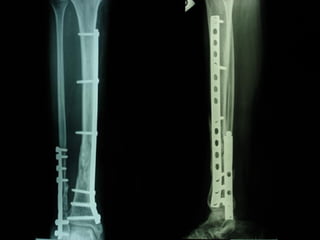

INDICAZIONI COMUNI Fratture sovracondiloidee Fratture intercondiliodee Fratture diafisarie distali PARTICOLARI Fratture con grave osteoporosi Fratture periprotesiche

VANTAGGI CHIRURGIA MININVASIVA Mini Open Inserimento della placca sottocutaneo per scivolamento Viti percutanee Preservazione dei tessuti molli Ridotto danno vascolare Rapida ripresa funzionale

F, 68 y

LISS  NCB

NCB